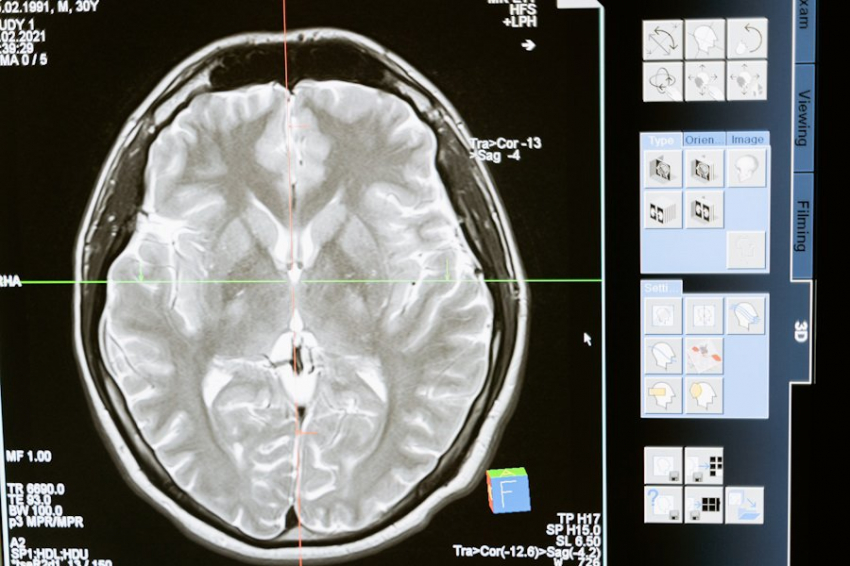

Согласно BlockChain24, современные системы машинного обучения уже демонстрируют свою эффективность в анализе медицинских изображений. Например, ИИ помогает обнаруживать рак на ранних стадиях с точностью, превышающей человеческие возможности. Это минимизирует вероятность пропуска опасных патологий и увеличивает шансы на успешное лечение.